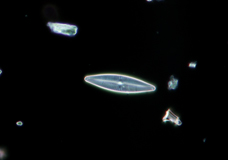

简易偏光

这是理想的观测双折射的样品,如胶原蛋白,淀粉样蛋白和结晶。

*有两种类型的分析仪可供选择:中间管式和物镜转换器滑盖式。

2.8-Dihydroxyadenine结晶,简易偏光,CFI Plan Fluor 40X,图片来自日本大学板桥医院临床检验科